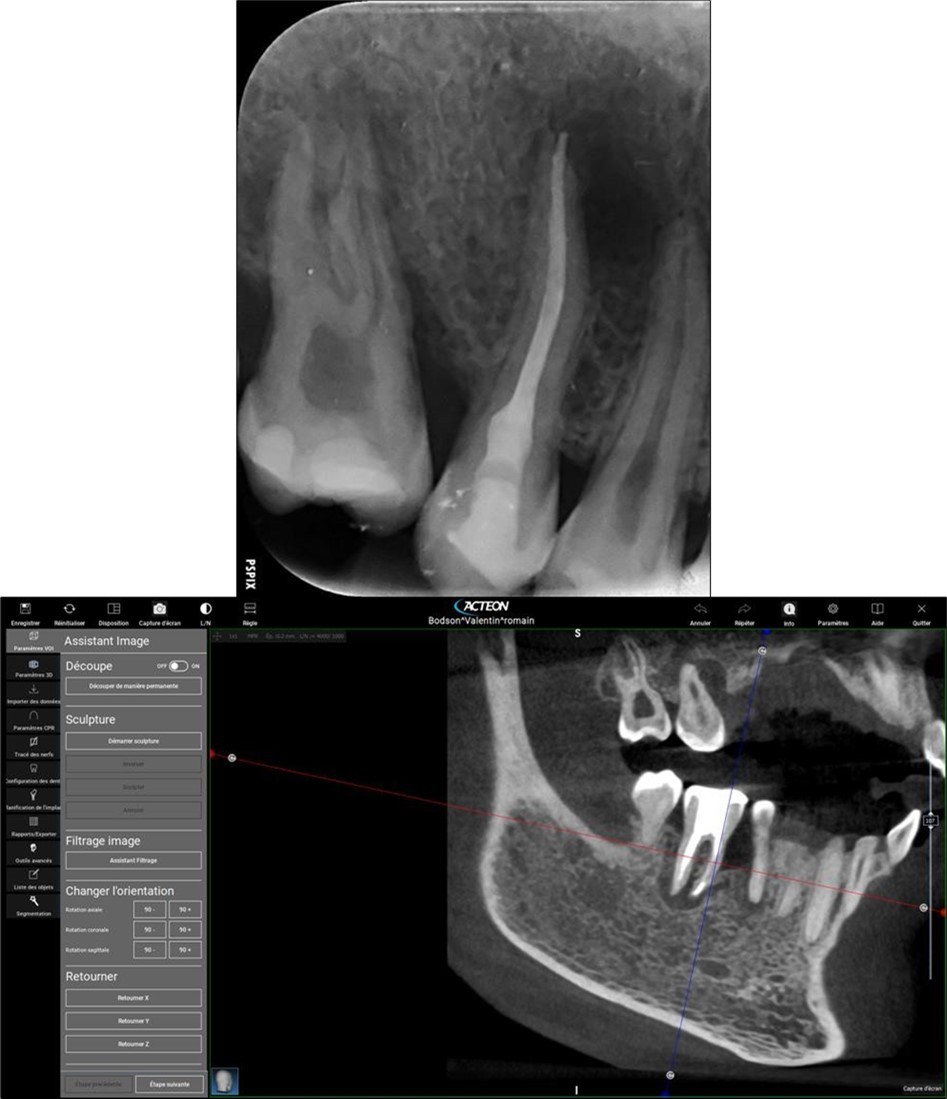

Periapical radiography (phosphorus number 2 plaque and X-MIND® Unity; Acteon) and cone-beam computed tomography (X-MIND® 3D; Acteon) (80 × 80, 150 Micron) were performed and showed periapical lesions on teeth 14, 15, 16, 24, 25, 26, 35, 36, and 46, as well as advanced endo-perio lesions on teeth 26 and 16. orthopantomogram (X-MIND® 3D; Acteon) and bitewings (phosphorus number 2 plaque and X-MIND® Unity; Acteon) also showed wide pulp chambers and roots canals. Figure 1, Figure 2

Figure 2.2. 3, 4, and 5 show periapical lesions on teeth 15, 16, 24, 25, 26, 35, 36, and 46.

Complete healing of periapical lesions and treatment of teeth 26 and 16 with advanced endo-perio lesions posed challenges due to the patient’s delayed supplementation. In this case, surgical endodontic procedures and the extraction of teeth with advanced endo-perio lesions were considered risky because of the underlying metabolic healing impairment. Figure 3

Figure 3.6. 7, 8, 9, and 10 showing postoperative periapical radiographs of these endodontic treatments.